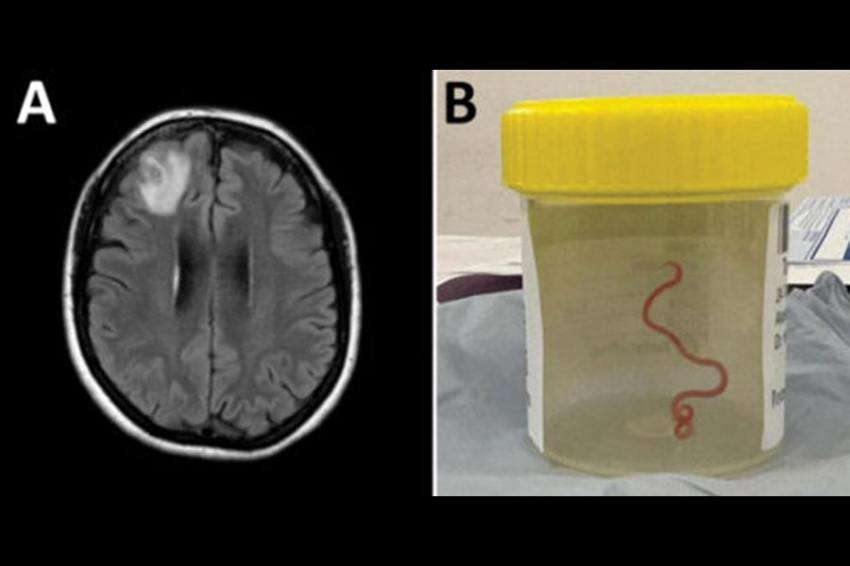

Как только печеночный сосальщик заражает муравья, в его тело проникают несколько сотен паразитов. Но только один попадает в мозг, где может повлиять на поведение муравья. Остальные печеночные сосальщики прячутся в брюшке муравья.

«Здесь могут быть сотни печеночных сосальщиков, ожидающих, пока муравей перенесет их в своего следующего хозяина. Они завернуты в капсулу, которая защищает их от желудочной кислоты хозяина, в то время как печеночный сосальщик, захвативший контроль над муравьем, умирает. Можно сказать, что они жертвуют собой ради других», — объясняет Брайан Лунд Фреденсборг.

Муравей-зомби: печёночный сосальщик заражает мозг муравья, заставляя его цепляться за травинку, и следующий хозяин — корова, овца, олень или другой травоядный — съедает её. Тем временем большая стая сосальщиков ожидает передачи в брюшке муравья.

Пасущийся: как только пасущийся человек проглатывает зараженного муравья, он также заражается печеночным двуустка. Печеночный сосальщик, захвативший контроль над мозгом муравья, погибает в желудочной кислоте хозяина. Большая стая в брюшной полости муравья защищена капсулой, которая растворяется в кишечнике хозяина только один раз. Здесь печеночные сосальщики попадают через желчные протоки в печень, где сосут кровь и развиваются во взрослых сосальщиков, которые начинают откладывать яйца, которые затем выделяются через фекалии животного-хозяина.